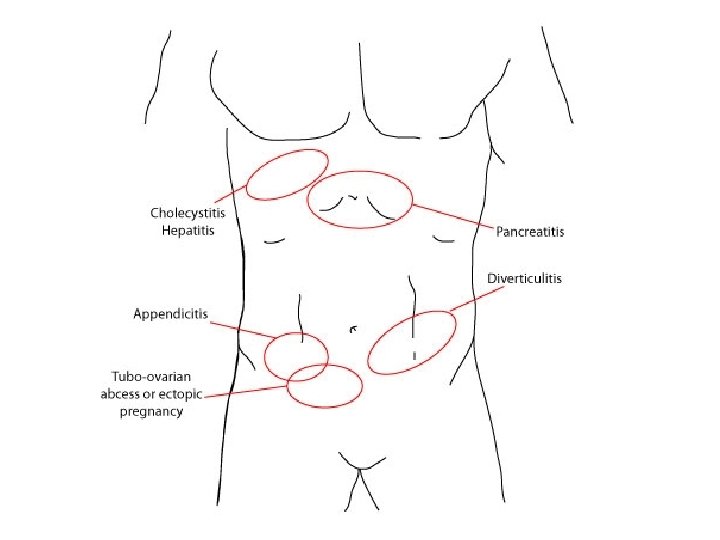

• KLINIKA: - Shenja kryesore eshte dhimbja abdominale e forte qe lokalizohet me veshtiresi nga i semuri. - Dhimbja: fillon ne regionin epigastrik, mund te perhapet edhe ne shpine ose ne shpatullen e djathte, por kryesisht perqendrohet ne kuadrantin superior dexter. - Eshte nje dhimbje me intensitet ne rritje. - Kjo dhimbje pasqyron tensionin dhe inflamacionin e mureve te kolecistes, si pasoje e obstruksionit kalkuloz te duktusit cistik.

• DHIMBJA: Vjen nga nje peristaltike e sforcuar per te kaluar pengesen. Me shpesh paraqitet rreth umbilikusit ne epigaster, per segmentet e siperme te zorreve te holla dhe ne kuadrantet inferior te abdomenit ne okluzionin e segmentit te poshtem te kolonit

KLINIKA: • DHIMBJA: Fillimisht e moderuar ne forme kolike ne regionin periumbilikal, me pas shnderrohet ne dhimbje te qendrueshme e zhvendosur ne kuadrantin inferior dexter.

EKZAMINIMET LABORATORIKE: - Hemogram: Leukocitoze - Ekzaminimi i urines: per diagnoze diferenciale DIAGNOZA DIFERENCIALE: - Kolecistit - Kolika renale dexter - Ulcer gastroduodenale e perforuar - Okluzion intestinal

RUPTURE e shtatezanise ektopike:

RUPTURE e aneurizmes se aortes:

KOLIKAT RENALE